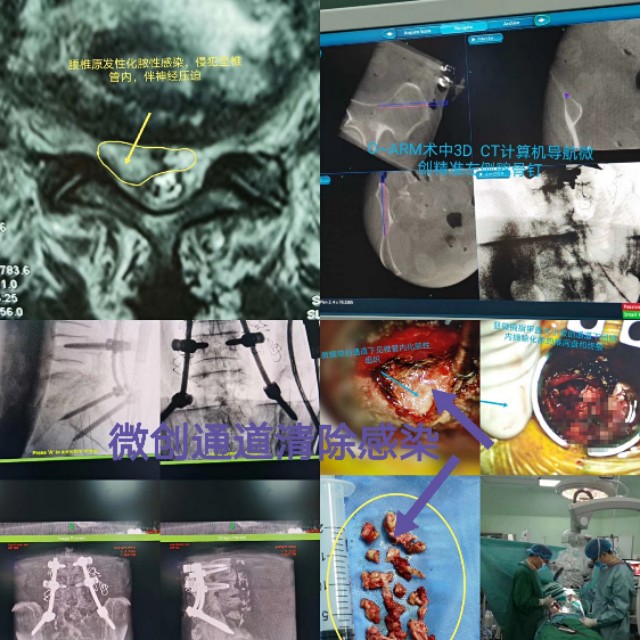

老人牙齿不好引起腰椎原发性腰5骶1化脓性感染,侵犯至椎管内,伴神经压迫。显微镜微创通道加导航辅助微创通道下间隙内感染清除,经微创入路行腰3腰4及导航下精准植入髂骨钉,钉道理想。深圳华大基因确诊细菌来源于牙齿������,术后一个月复查,病人己完全康复������